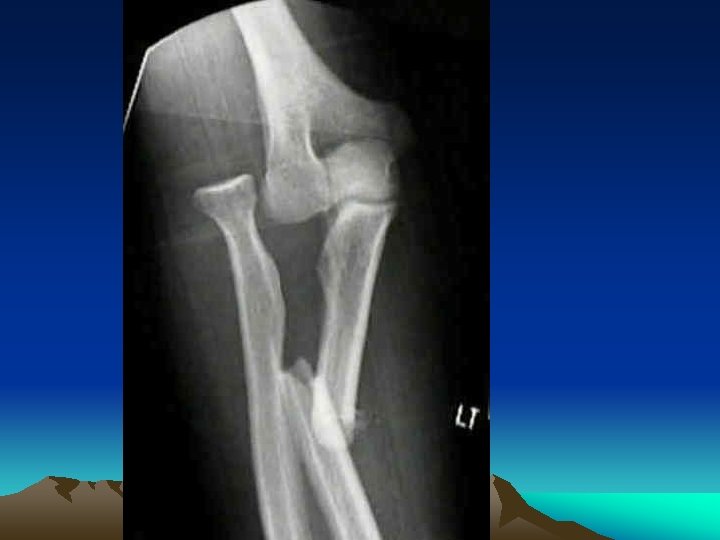

Mechanisms Indirect Force on Long Bones 3) Angulating + Axial compression Transverse line + Triangular “Butterfly”

Mechanisms Indirect Force on Long Bones 4) Angulating + Axial compression + Twisting forces (short oblique pattern)

Diagnosis C- Description of X-ray : 1) Situation : side, site, localization 2) Pattern : line of fracture 3) Displacement : a) Shift : lateral, medial, anterior, posterior b) Tilt : angulations c) Twist : rotation , internal, external d) Shortening: overriding, impaction